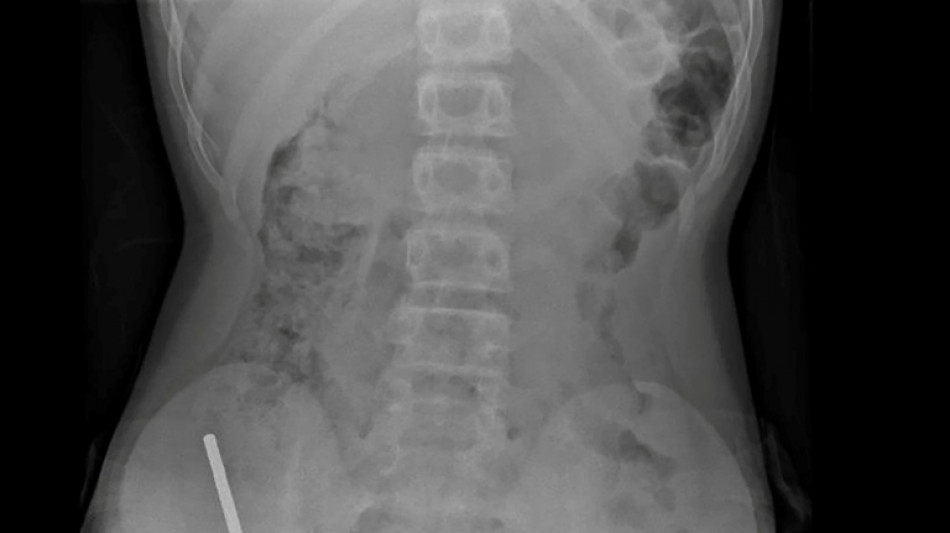

Nouvelle-Zélande: un adolescent opéré après avoir ingéré près de 100 aimants achetés sur Temu / Photo: © NEW ZEALAND MEDICAL JOURNAL (NZMDJ)/AFP

En Nouvelle-Zélande, un adolescent de 13 ans s'est vu retirer plusieurs parties nécrosées de ses intestins après avoir avalé près d'une centaine d'aimants achetés en ligne sur le site Temu, a rapporté vendredi une revue médicale.

"Il avoué avoir ingéré entre 80 et 100 aimants puissants au néodyme, de 5x2mm environ, une semaine plus tôt", indique un rapport des médecins de l'hôpital de cet hôpital, publié dans le New Zealand Medical Journal (NZMJ).

Les médecins ont déclaré que la pression exercée par les aimants avait provoqué une nécrose dans quatre zones de l'intestin grêle et du gros intestin du garçon.